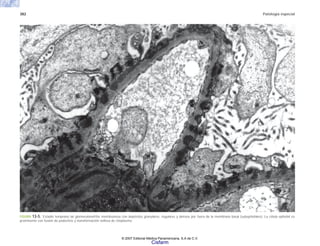

FIGURA 6-1. Ultraestructura de los macrófagos en la rata. a) Macrófago peritoneal. b) Macrófago alveolar.

(a)